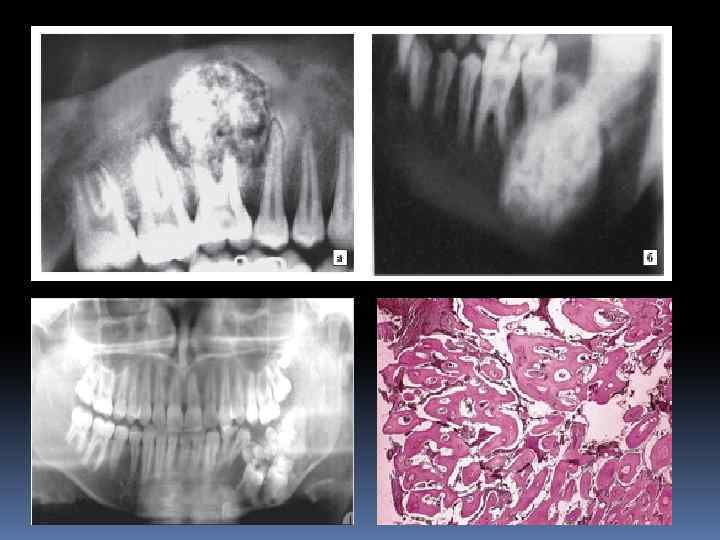

Амелобластома(адамантинома) Доброкачествен ная опухоль, развившаяся из эпителия, в которой формируются структуры, напрминающие по гистологическом у строению эмалевый орган зуба.

Одонтома Доброкачествен ная одонтогенная опухоль, состоящая из различных зубных тканей, это порок развития зубных тканей. Одонтомы бывают составные и сложные.

Цементома Доброкачественная опухоль из одонтогенной соединительной ткани, которая дифференцируется в цемент зуба. Формы цементом: -доброкачественная цементобластома; -цементирующая фиброма; -периапикальная цементная дисплазия; -гигантоформная цементома.

Кисты челюстей. Классификация 1. Эпителиальные: Одонтогенные кисты: - первичная киста (примордиальная кератокиста); - киста прорезывания; - пародентальная (периодонтальная); - десневая; - зубосодержащая; - фолликулярная; - корневая (радикулярная). Неодонтогенные кисты: - киста резцового канала (носонёбного протока) - глобуломаксиллярная киста (фиссуральная); - киста носогубная (носоальвеолярная, преддверия полости рта); - холестеатома.

2. Неэпителиальные: - костные кисты (аневризматическая, травматическая, геморрагическая) 3. Одонтогенные кисты воспалительного происхождения: - корневые; - зубосодержащие; - пародонтальные (условно).

Радикулярная киста